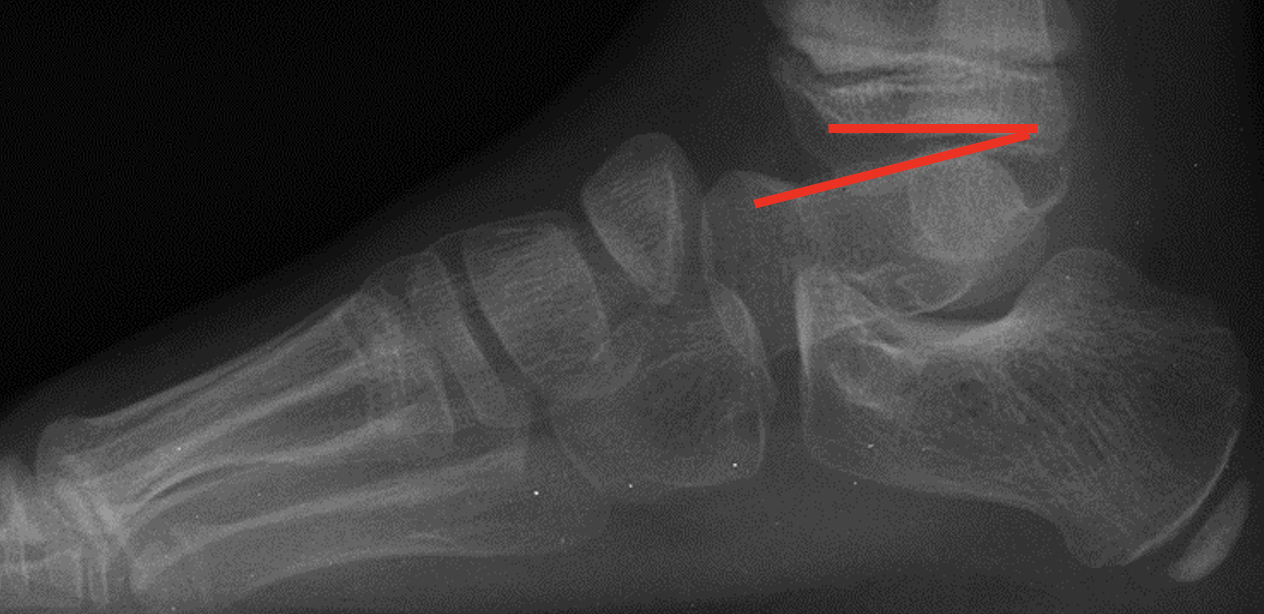

As the Ponseti grew in popularity, I noted significant discrediting of surgical options. Well long-term studies on the Ponsetti are starting to surface, and it is not without its own problems. Kids are lost to follow-up, not braced appropriately, and just like we saw in long-term studies with the posteromedial release, there is a lot of undercorrection. Casting cannot and will not ever achieve what the Cincinnati release can. Although the Ponseti may not have the complications of the Cincinnati, X-ray data reveals that the Ponseti cannot and does not correct everything, most critically, talocalcaneal angles. You can not solve a clubfoot with an Achilles tenotomy and an overly aggressive casting. As these kids develop, I see residual met adductus and calcaneal varus, along with casting complications like flat top talus and met primus elevatus. I then see that they will develop DJD just like posteriomedial and Cincinnati releases. Haasbeck and team in 1997 reported that the Cincinnatti required fewer procedures than the posteromedial release over the life of their study.14 Thomas performed a systematic review in 2019, concluding that the longer the study follow-up, the greater the relapse rate and the poorer the results of the Ponseti.15 For most of us who have done clubfeet surgery for many years, this is no surprise. Among the 46 studies meeting inclusion criteria, they saw as high as 67 percent required future surgeries to address relapse.15

One of the most disturbing complications with any casting is the development of flat top talus. Overly aggressive attempts to dorsiflex the ankle often lead to met primus elevatus, but the flat top talus ruins the ankle joint during development. When I work with residents and students, I always stress the importance of avoiding dorsiflexion completely during the casting phase simply because I do not want to create a deformation of the talus. I reserve all of my sagittal plane correction for the Achilles lengthening and posterior capsule release. Unfortunately, I see more and more cases of flat top talus as a result of the Ponseti method. Khan and colleagues in 2021 reported a significant increase in their study and review of the literature, blaming it solely on overly aggressive casting and manipulation.16

So, to summarize, true congenital clubfeet have abnormal talar bodies, which lead to abnormal ankle and subtalar joints with short Achilles and tight posterior tibial tendons. Regardless of treatment, there is nothing anyone can do to make the talus a normal bone. Many of these cases can and will develop additional deformities. Only the Cincinnati release can address every issue associated with the deformity, but it is NOT a cure. The Ponseti procedure is a total compromise, also NOT a cure. The sooner everyone treats the Ponseti as a compromise, I believe we will be far happier with the outcomes. I remember discussing this with others treating pediatric orthopedic issues during the rise of the Ponseti in the early 2000s. We all agreed, undercorrecting the deformity will lead to more surgeries and residual deformities. Until we all face the reality that clubfeet are a genetic deformity and not just a positional deformity, we will never make them perfect. Thus, athletes and the military will put any and all clubfeet patients to the test. There is no doubt that exceptions exist, but in time, at least based on our limited review of over 1000 clubfeet and 250 cases we saw in the military, no one is immune to complications, arthritis, and ultimately disability.